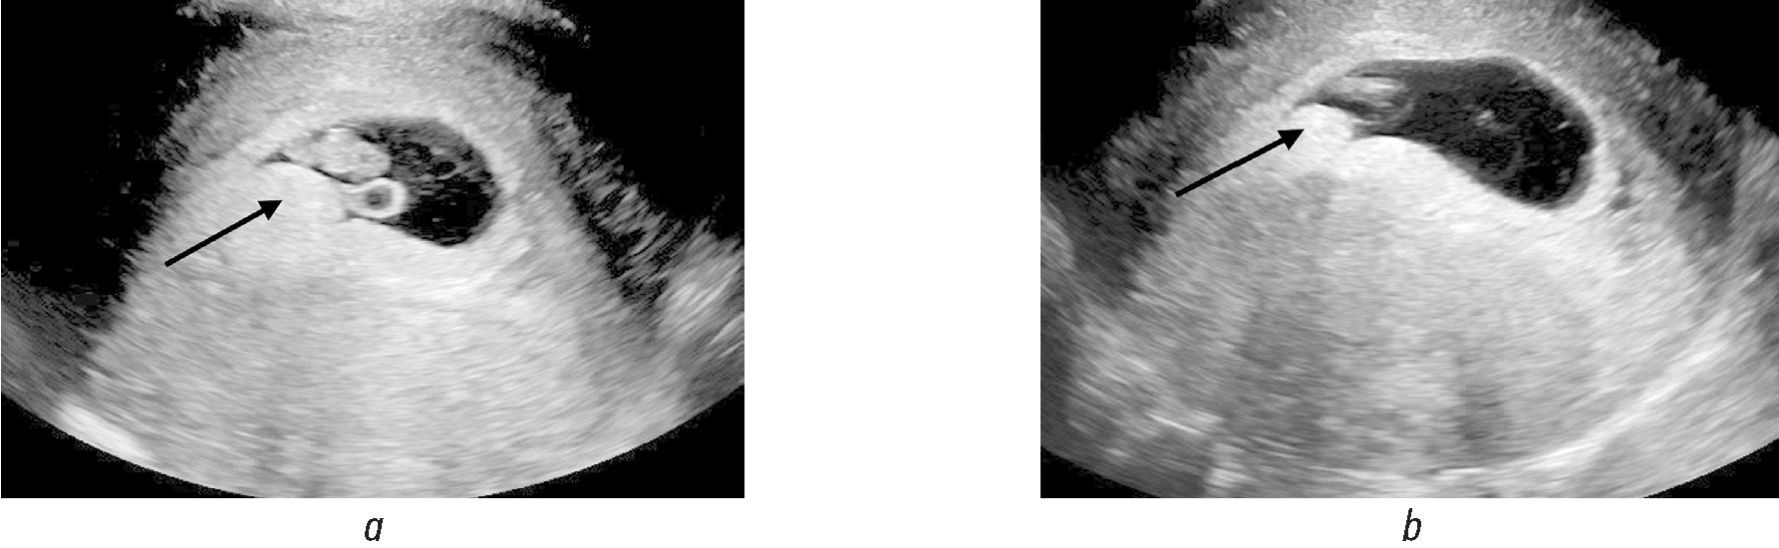

Наиболее частые и характерные сонографические признаки ХВ (рис. 1, а, b; рис. 2, а–c) [1, 2, 4, 6, 10–12]:

Рис. 1. На трансвагинальных сонограммах (а, b) визуализируется солитарное хориальное выпячивание (стрелки) солидной эхоструктуры, однородно повышенной эхогенности, сопоставимое по эхогенности с хорионом

1) выпячивание хориона в полость плодного яйца в первом триместре;

2) выпячивание локализуется в месте прикрепления пуповины к хориону или в непосредственной близости;

3) форма выпячивания овоидная или полипоподобная;

4) выпячивание чаще образует острые углы с поверхностью хориона;

5) выпячивание имеет разную эхоструктуру и эхогенность: солидную или жидкостную, от гипоэхогенных до гиперэхогенных, часто в виде центральной гипоэхогенной области с периферическим гиперэхогенным ободком;

6) хориальное выпячивание бессосудистое при цветовом и/или энергетическом допплеровском картировании;

7) в режиме реального времени в выпячивании визуализируется завихрение эхосигналов;

8) чаще одиночное, реже множественное.